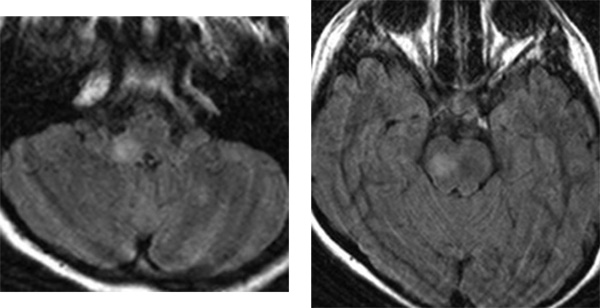

10歳のNF-1の子どもに発見された延髄のグリオーマ

10歳の時のMRI

延髄(左の写真)と中脳(右の写真)にFLAIR画像で病変が見られます